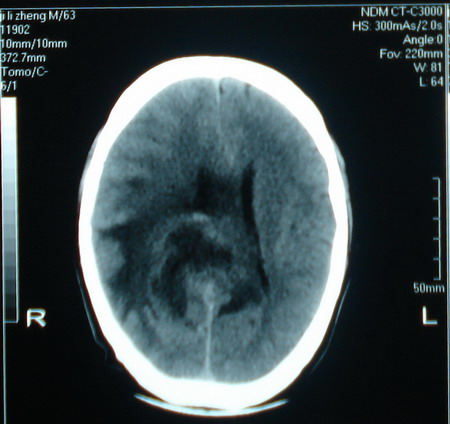

标题: CT13794:M63Y,头颅CT平扫 [打印本页]

标题: CT13794:M63Y,头颅CT平扫

男,63岁,头痛,呕吐,意识模糊一周。无发烧及感染史。

脑膜瘤可能。建议增强或mr检查

小肿瘤大水肿,考虑转移瘤

脑肿瘤 1 室管膜瘤 2 转移瘤

支持右侧丘脑恶性胶质母细胞瘤可能性大,建议增强进一步检查。